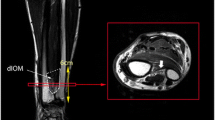

Twelve fresh-frozen cadaver upper extremities (60–86 years, mean 73 years), precut at the mid-humerus level, were thawed in a warm isotonic saline solution. Each upper extremity was braced in elbow extension and forearm supination for imaging studies on a 1.5 Tesla MR scanner (GE Medical Systems, Milwaukee, WI, USA). Axial FSE images were obtained utilizing a torso coil with a repetition time (TR) of 3550 ms, an echo time (TE) of 89 ms, a field of view (FOV) of 12×12 cm with a 256×256 matrix. The slice thickness was 5 mm with a 2-mm skip. Thirty-five images were obtained for each specimen and reviewed on an AGFA IMPAX workstation (Gavaert, Mortsel, Belgium). The length of the radius was measured on a coronal scout image using an electronic caliper. The position of each axial image measurement was expressed as a percentage distance from the radial styloid process to the radial head. The axial images closer than the midpoint of the radius (closer to the radial styloid) are less than 0.5. The axial images distal to the midpoint of the radius (closer to the radial head) are greater than 0.5. Each slice was reviewed and the thickness of the IOM was measured at the radial, central and ulnar locations (Fig. 1). The thickness of each section was grouped by location and plotted against the position along the radius. The central fiber bundle of the IOM was determined by locating the largest thickness measurements with a distal oblique direction from the radius to the ulna (Fig. 1). Similarly, the dorsal oblique bundle was determined by locating the largest thickness measurements with a proximal oblique direction from the radius to the ulna (Fig. 1).

A The IOM is composed of several anatomic locations. Distally the membrane is very thin without discrete fiber bundles. At the mid-forearm level, there are several accessory fiber bundles demonstrating distinct orientation from the radius to their ulnar insertion. Just proximal to the mid-forearm is the location of the main fiber bundle. On the dorsal aspect of the proximal forearm the oblique bundle has its origin on the ulna and inserts distally on the radius. The dashed line indicates the level of the axial image in B. B Thickness measurements were obtained using laser and MRI at three locations: ulnar, central, and radial. This image demonstrates the various measurement locations at the mid-forearm level